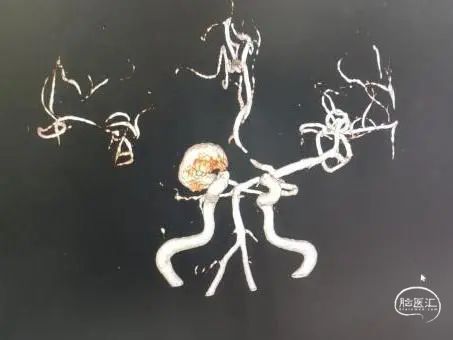

术前影像

脑动脉DSA提示右侧颈内动脉C5床突段动脉瘤。

右侧床突段载瘤动脉远端血管直径为1.8mm,载瘤动脉近端血管直径为5.2mm,瘤体宽13.1mm,瘤体最大宽度21.8mm。